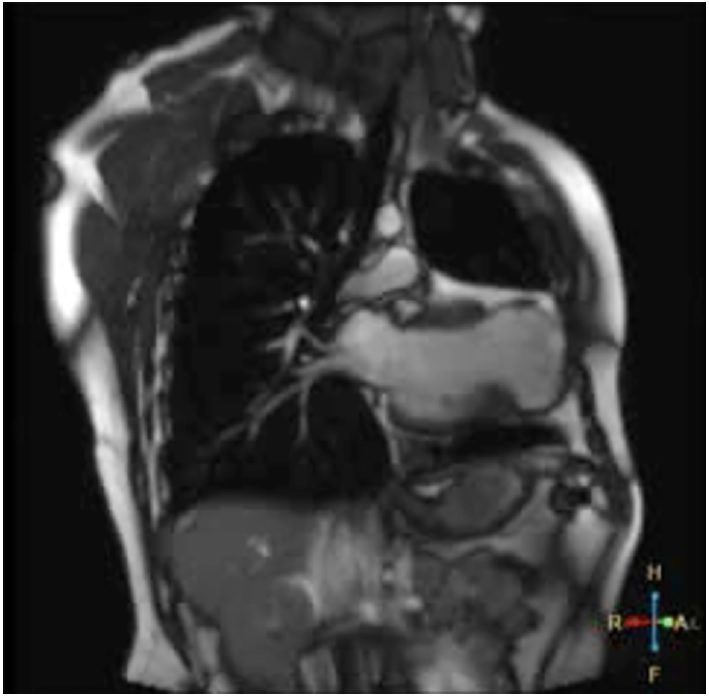

We present the case of a 30-year-old male patient with history of non-atherosclerotic dilated ischemicnecrotic cardiomyopathy, with reduced left ventricular ejection fraction (LVEF) (35%) and ventricular aneurysm (Figure 1), as a result of extrinsic iatrogenic lesion following anterior descending artery suture due to gunshot wound and urgent surgery. He subsequently underwent various hospitalizations for recurrent sustained monomorphic ventricular tachycardia (SMVT) (Figure 2a), leading to implantable cardioverter defibrillator (ICD) placement and substrate ablation, with favorable outcome.

Fig. 1 T2 sequence magnetic resonance coronal section showing left ventricular dilation, presence of apical aneurysmatic sac, myocardial thinning and low-intensity signal.